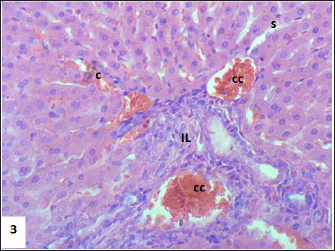

Mouse liver from the control group shows a normal radiant arrangement of the hepatic cells (Fig. 1). Pathological changes in treated liver sections showed an increase in the immune cells’ infiltration, and marked congestion were observed in almost all mice. In group 1, there was hemorrhage, congestion, and degenerated cells (Fig. 2). In group 2, there was congestion of the central vein, infiltration of immune cells, and degeneration of hepatocytes (Fig. 3). Whereas in group 3, the previously mentioned changes were markedly intensified with severe hemorrhage and marked sinusoidal dilatation (Fig. 4). Mouse kidney of control group shows normal cellular appearance (Fig. 5); however, pathological changes in treated kidneys sections reveals congestion, tubular necrosis and cast in some tubule’s lumen, group 1 (Fig. 6). In group 2, there was congestion, tubular necrosis, necrotic debrites in the tubuli lumen and cast (Fig. 7). Whereas in group 3 there was marked congestion, tubular and cellular necrosis, necrotic debrites in the tubular lumen and degenerated cells (Fig. 8).

Fig. 3. Section of mouse liver fed with 2 mg/kg Lorazepam showing congestion of central vein (C), and sinusoidal dilatation (s), ballooning degeneration of some of hepatocytes, pyknotic cells, marked steatosis and congestion (cc) with some apoptotic cells (ap) (H and E, ×400).